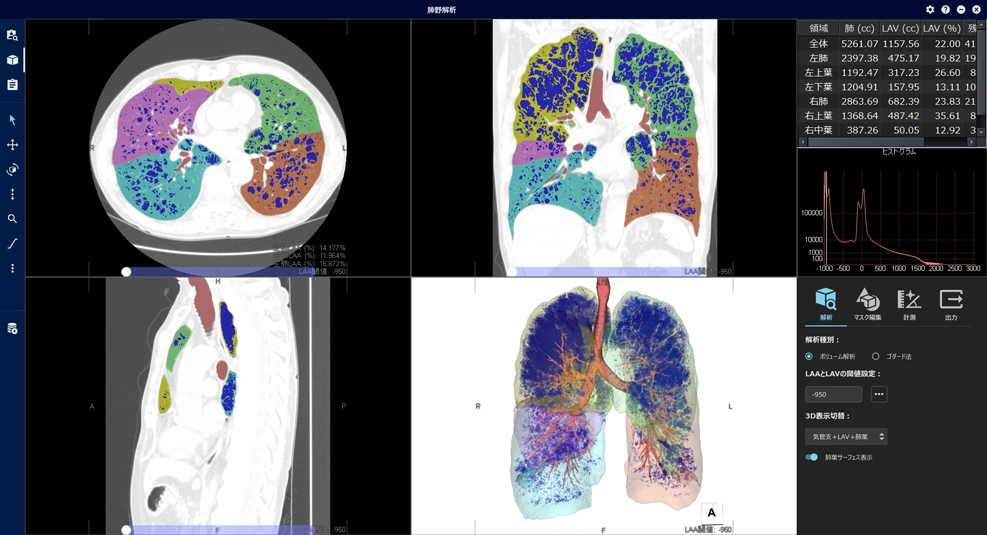

胸部のCT 第4版 | 村田喜代史, 上甲 剛, 村山貞之, 酒井文和 |本。胸部のCT 第4版 | 村田喜代史, 上甲 剛, 村山貞之, 酒井文和 |本。CC3 胸部CTの読影 - YouTube。kokuu 雑穀米 ホワイトブレンド グルテンフリー 2袋。CANON社製新型CT装置を導入 | 新柴又駅前クリニック(脳神経外科)。腹部CTを読影する上で重要な脂肪ウインドウとは? - YouTube。胸部CTの読影の基礎【働くのに必要な知識を最短で習得する方法。胸部CT画像の読影を支援するEIRL Chest CTの販売を開始 - エル。見逃しを防ぐための腹部CTの読影の順番|ごろ〜にゃ@放射線科医。18203920 | 腹部CT CBT | M3E Medical。体幹部領域-Aquilion PRIMEの各領域における技術 - 東芝。CT¹⁾検査|検査ガイド|患者さん向けガイド|原三信病院。腹部CT検査 胆石 - 医療のイラスト・写真・動画、素材販売サイト。胸部と腹部のCTに関する専門書、最新の知見を網羅。- 書籍名: 胸部のCT 第4版- 書籍名: 腹部のCT 第3版- 出版社: MEDSi- 書籍の状態: 良好- ISBN: 9784895921877- ISBN: 9784895921860ご覧いただきありがとうございます。○バラ売り希望にも対応します。(価格は応相談)コメントください!○未使用ですが、自宅保存のため運搬による傷が少しあります。○未使用のためメモなどはありません。カバーも目立った傷はありません。○できるだけ早く発送します。お急ぎの方はコメントください。